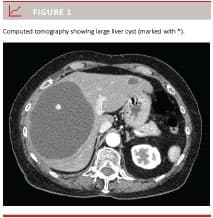

Cysts in the liver are present in approximately 5% of the population. The majority of patients have so-called simple cysts which are non-neoplastic and non-infectious cysts [1, 2]. Most patients are asymptomatic, but for those with symptoms, pain is the predominant complaint. On diagnostic imaging, for example computed tomography (CT), simple cysts are thin-walled with no septations (Figure 1), whereas infectious cysts are typically thick-walled, and neoplastic cysts often have nodules in the wall [1].